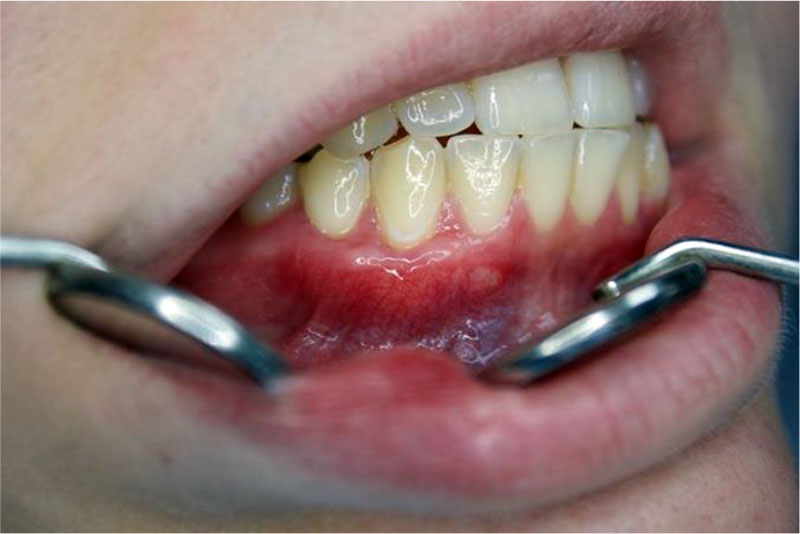

Patient A., 32 years old. Diagnosis: By 06.01 Recession of the gingiva, Miller class I. Local recession in the region of the 43 tooth (Fig. 3). The biotype of the gingiva is medium (1.0 mm), the gingival papillae are normal. Orthodontic treatment is planned. Preoperative treatment of the oral cavity was performed with 0.12% chlorhexidine solution for 1 minute. Under infiltration anesthesia Sol. Ultracaini D-S 1.7 ml performed an intrasulcular incision using a microsurgical scalpel (MANI, Japan). The exposed surfaces of the roots of the teeth were carefully processed to the height of the loss of clinical attachment in 4 stages: ultrasonic treatment, instrumental machining using Gracie Mini-Five curettes (Hu-Friedy, USA), polishing and smoothing of the tooth root surfaces using periodontal burs RA (Komet, Russia), drug treatment with the application of lincomycin hydrochloride 30 mg / ml for 2 minutes. Tunnel raspatory (Hu-Friedy, USA) exfoliated the mucous split flap and prepared the tunnel bed. A free gingival autograft was taken from the hard palate (Fig. 4) and its de-epithelization (Fig. 5), adapted in size and introduced into the tunnel bed using guides positioning sutures PTFE 5.0 (Golnit, Russia) (Fig. 6). The wound was sutured using double twisted sutures PTFE 5.0 (Golnit, Russia) (Fig. 7). Postoperative drug treatment was performed with 0.12% chlorhexidine solution. Removal of stitches after 14 days. The result after 1 month is the complete elimination of gingival recession in the area of tooth 43, but unevenness of the keratinized gingiva is observed in the area of the base of the interdental papillae (Fig. 8).

Figure 8. Result in 1 month. Complete defect coverage in the area of 43 teeth. There is an additional volume of keratinized gingiva in the area of 43 teeth.